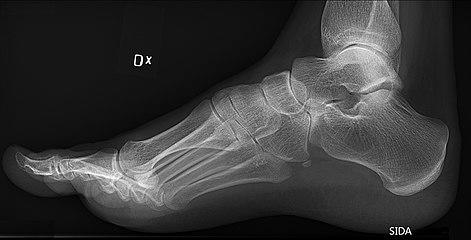

Charcot-marie-tooth foot.jpg

High arch in foot of a person with a hereditary neuropathy